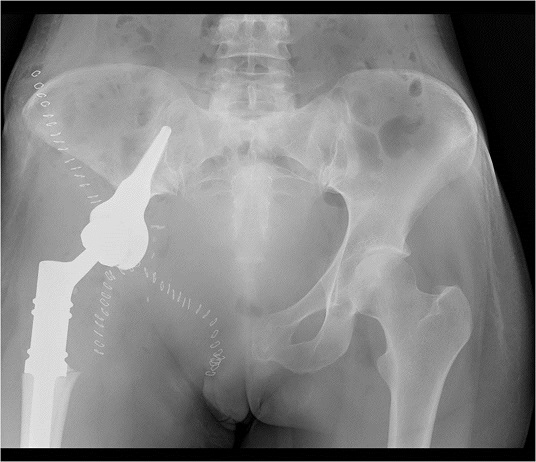

После операции выполняется контрольный снимок эндопротеза в 2-х проекциях:

В марте 2014 года в нашей клинике пациентка оперирована. Ей выполнена резекция костей таза с удалением опухоли и эндопротезированием. Морфологический диагноз по данным исследования операционного материала - хондробластическая остеосаркома правой лонной кости, Grade 3, с инвазией мягких тканей. В краях резекции опухолевого роста не выявлено, как и во всех удаленных лимфатических узлах.

Послеоперационный период протекал без осложнений. В октябре 2014 года пациентка уже могла передвигаться самостоятельно без опоры. В настоящее время чувствует себя удовлетворительно.

После необходимой подготовки пациентке выполнена резекция костей таза с удалением опухоли и эндопротезированием. В послеоперационном периоде осложнений не было, пациентка довольно быстро вернулась к самостоятельной двигательной активности. Реабилитация после проведенного хирургического вмешательства была настолько полной, что в 2014 году пациентка смогла выносить и родить ребенка.